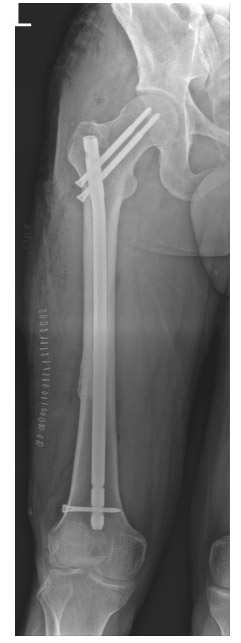

Post-surgery: The image shows bone cement and intramedullary nail placement in the mid-section of the right femur.